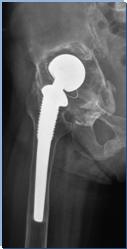

术前X线片示右侧全髋关节置换术后,假体柄周围见透亮影,考虑假体柄松动

右髋翻修术后髋关节假体稳定,假体位置角度良好,可早期下地活动锻炼